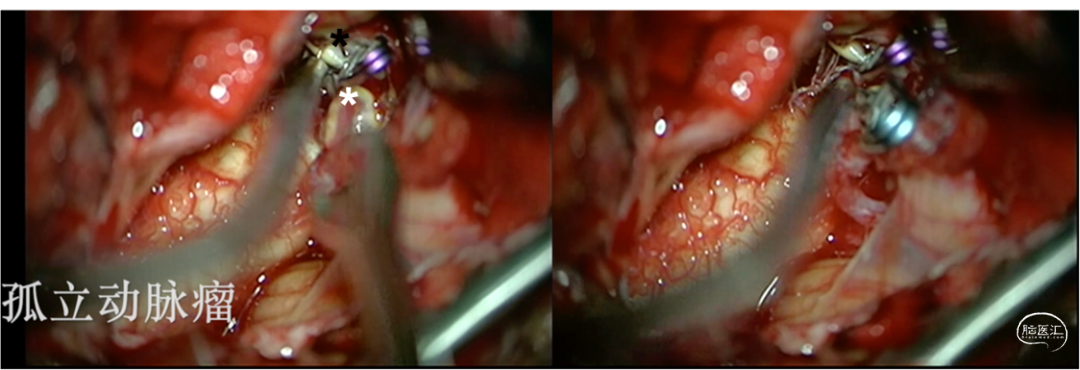

3.探查载瘤血管,分别夹闭动脉瘤流入道及流出道,行动脉瘤孤立术(图6)。

图6.术中展示先后夹闭PICA段动脉瘤流入道(黑色*)及流出道(白色*),进行动脉瘤孤立。